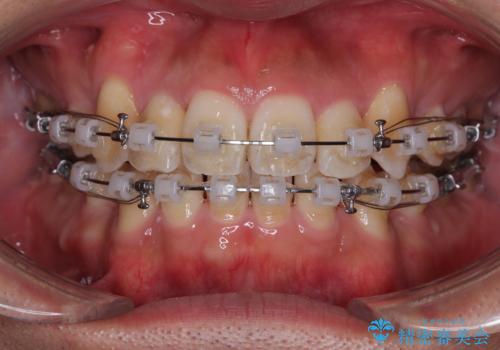

八重歯と前歯のガタガタを抜歯矯正で治療|クリアブラケット使用例

- 矯正装置

- クリアブラケット

- 「八重歯を治したい」とご相談いただいた患者様の症例をご紹介します。

上下の前歯部に強い叢生(ガタガタの歯並び)があり、そのまま歯を並べると出っ歯になってしまう可能性がありました。

そこで、上下左右の第一小臼歯を抜歯し、歯が並ぶためのスペースを確保し叢生を解消する治療計画を立てました。

矯正装置は、審美性と費用面のバランスを考慮して、プラスチックブラケットとメタルワイヤーを使用しました。

透明感のあるブラケットを用いたため、従来の金属装置よりも目立ちにくく、日常生活での見た目の不安も軽減できます。